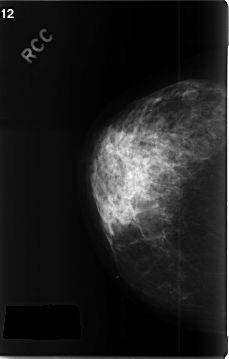

C_0343_1.RIGHT_CC

RIGHT_CC LINES 4656 PIXELS_PER_LINE 2968 BITS_PER_PIXEL 12 RESOLUTION 50 NON_OVERLAY